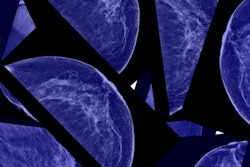

In contrast to incidence rates, breast cancer death rates have decreased in most countries, especially high-income ones, due to improved breast cancer treatment and early detection through mammography, the group wrote. However, 10 countries are the exception to this rule: Colombia, Ecuador, Japan, Brazil, Egypt, Guatemala, Kuwait, Mauritius, Mexico, and Moldova.